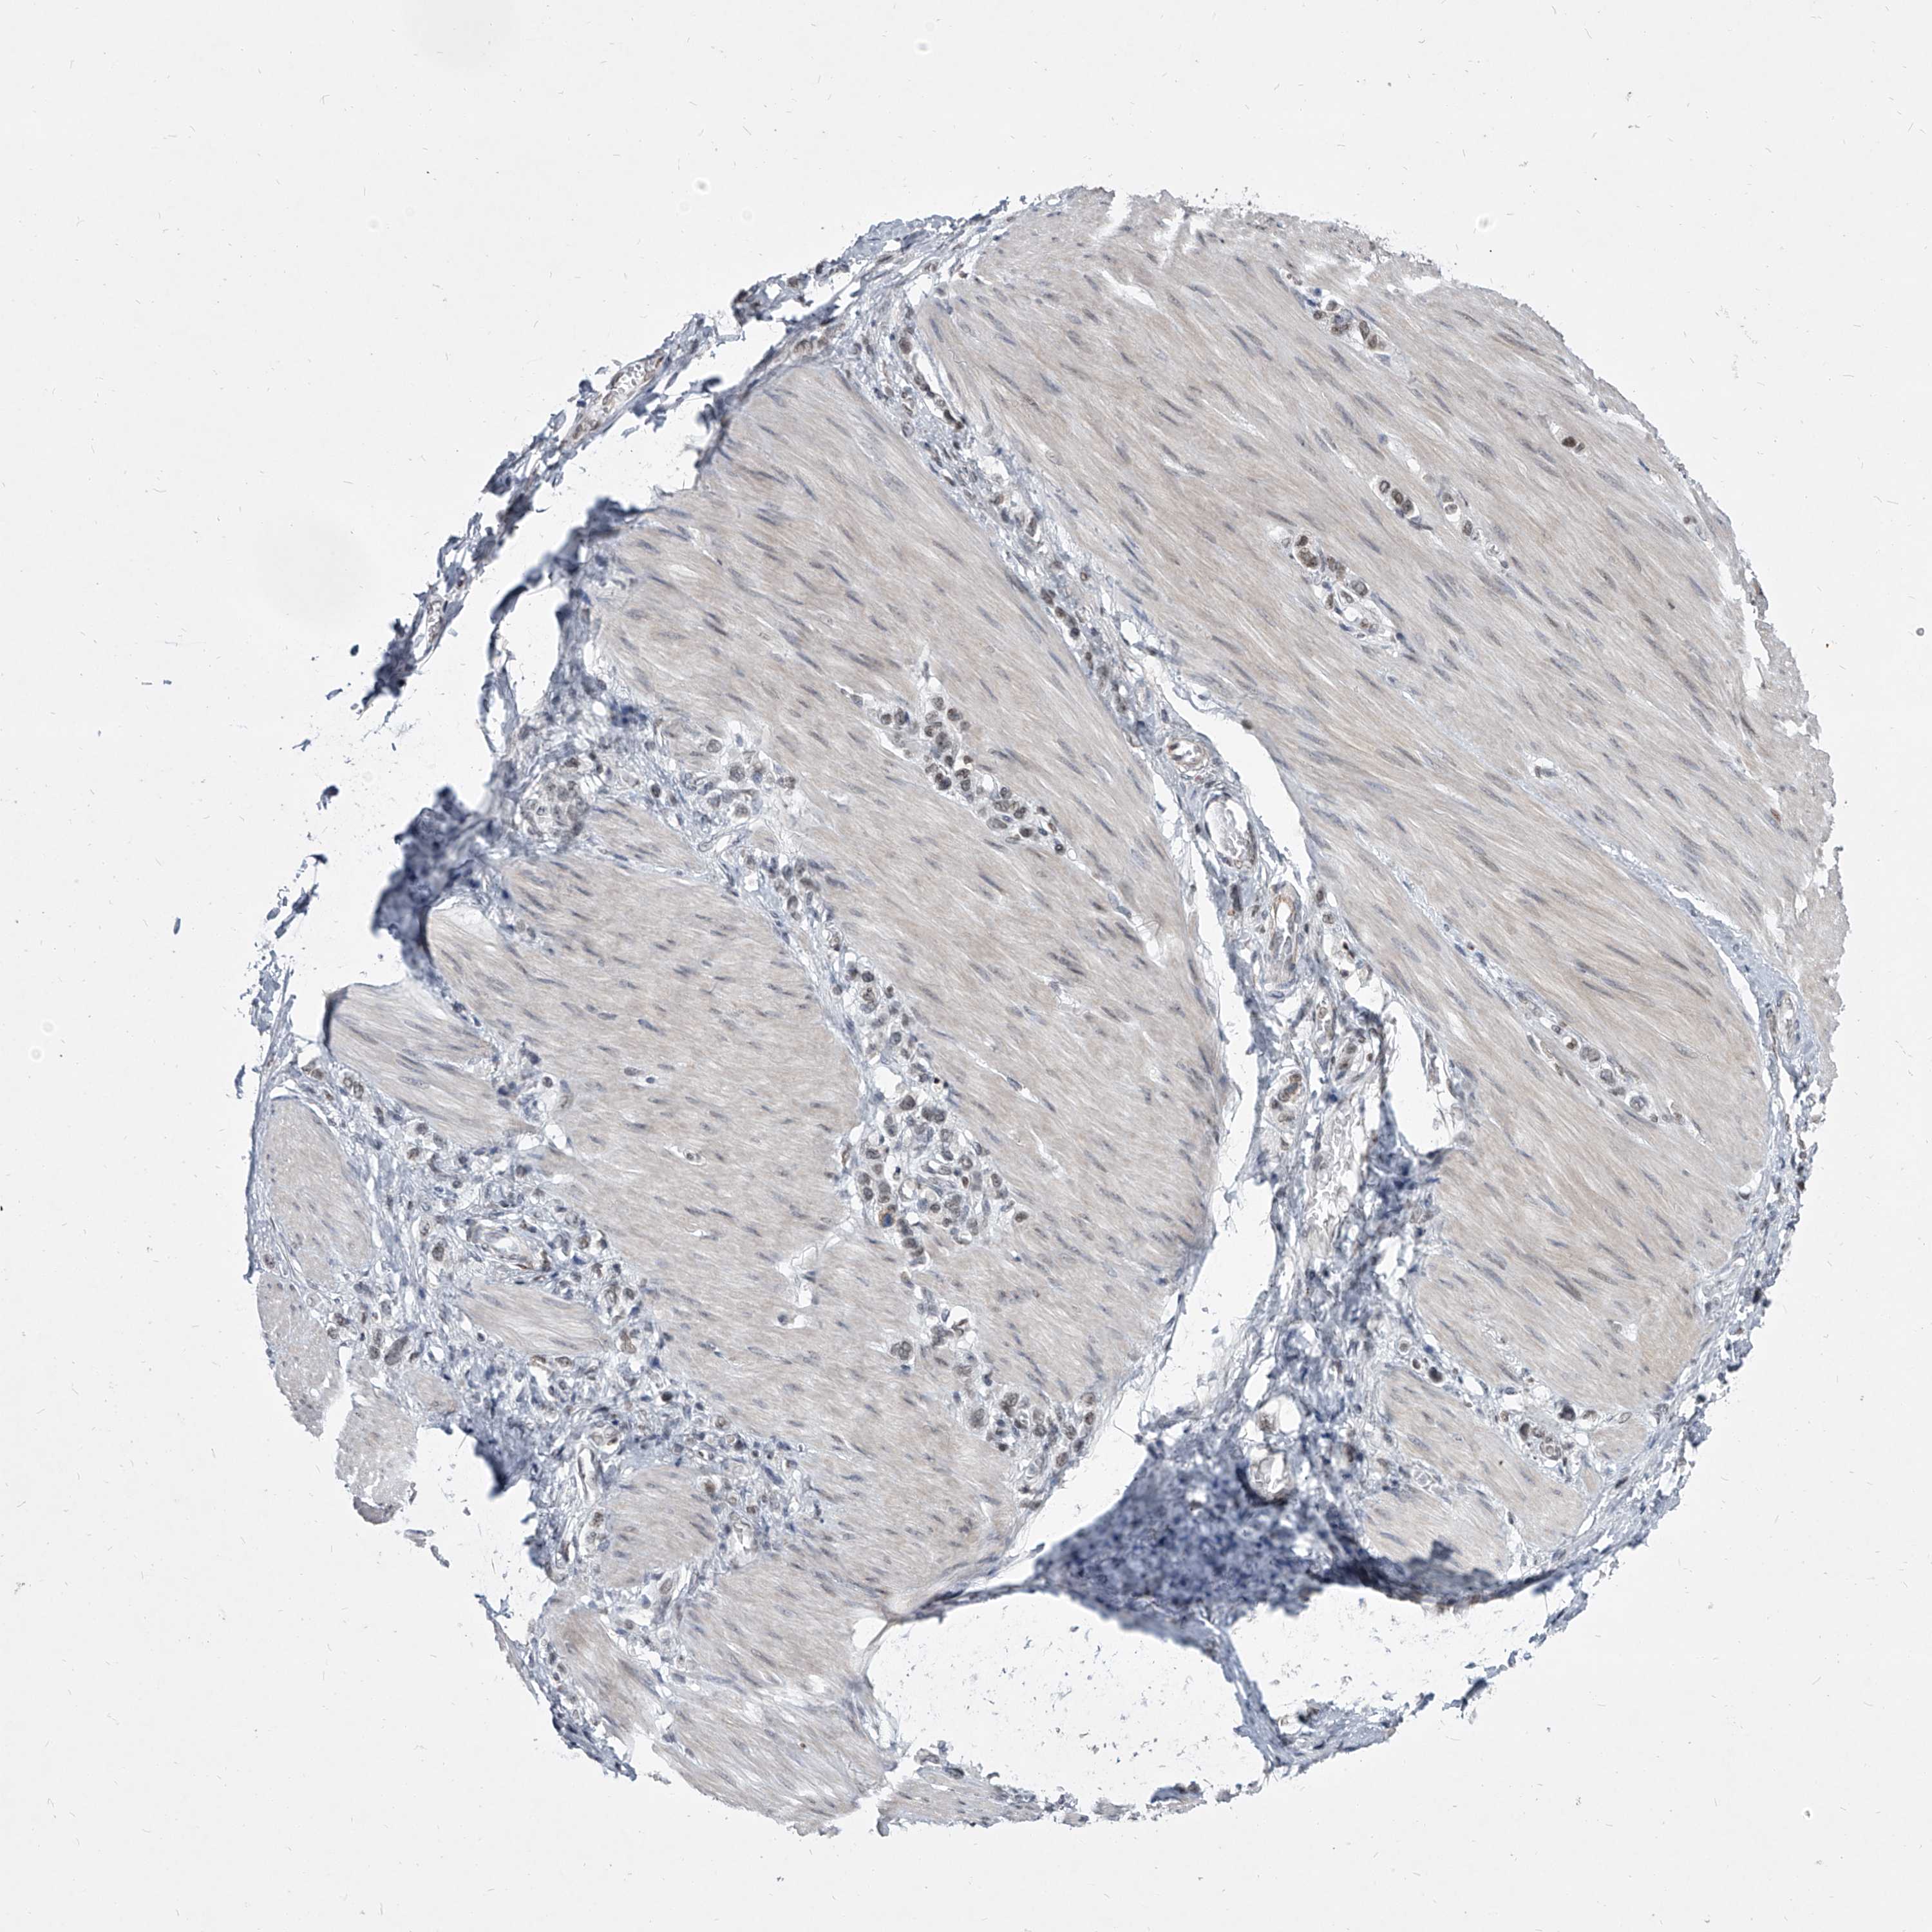

STOMACH CANCER - Protein expressioni

A mouse-over function shows sample information and annotation data. Click on an image to view it in a full screen mode. Samples can be filtered based on level of antibody staining by selecting one or several of the following categories: high, medium, low and not detected. The assay and annotation is described here.

Note that samples used for immunohistochemistry by the Human Protein Atlas do not correspond to samples in the TCGA dataset.

Antibody stainingi

Antibody staining in the annotated cell types in the current human tissue is reported as not detected, low, medium, or high, based on conventional immunohistochemistry profiling in selected tissues. This score is based on the combination of the staining intensity and fraction of stained cells.

Each image is clickable and will lead to virtual microscopy that enables deeper exploration of all samples and also displays staining intensity scores, fraction scores and subcellular localization as well as patient and tissue information for each sample.

Antibody HPA031600

Staining

High

Medium

Low

Not detected

Intensity

Strong

Moderate

Weak

Negative

Quantity

>75%

75%-25%

<25%

None

Location

Nuclear

Cytoplasmic/membranous

Cytoplasmic/membranous,nuclear

Adenocarcinoma, NOS